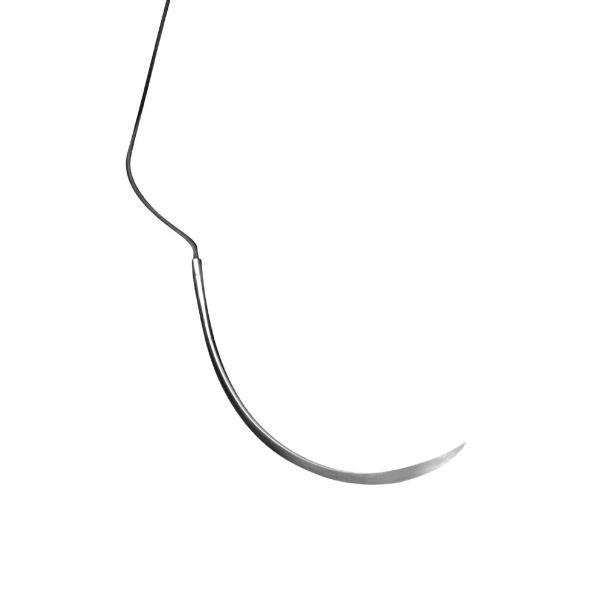

PSN719S SEDA 5/0 C-17 HU FRIEDY 220815

Seda trenzada de calidad superior. Sin escalón entre la aguja y el material de sutura, manteniendo ambos el mismo diámetro. El diseño de la punta, de máximo afilado, reduce un 20% la fuerza de penetración en el tejido. Aguja de sección triangular. Longitu